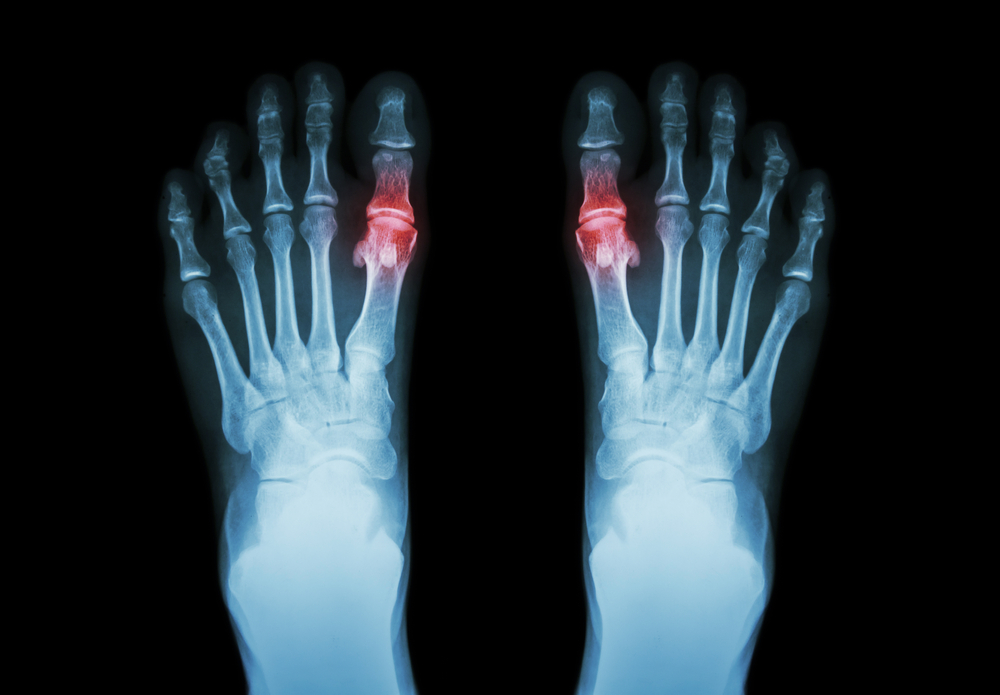

По рентгенографии суставов характерные изменения выявляются при хроническом подагрическом полиартрите. Рентгенологическая картина обнаруживает наличие остеопороза, на фоне которого определяются очаги просветления в области эпифизов и суставов размером до 2-3 см; при глубокой запущенности процесса — разрушение костных эпифизов с их замещением скоплением уратных масс. Специфические признаки подагры на рентгенограммах определяются по истечении 5 лет от манифестации заболевания.

А) рентгенография суставов – выявляет изменения при хроническом подагрическом артрите; изменения суставов и эпифизов в виде круглых «штампованных» очагов просветления различного диаметра (из-за костных тофусов); симптом «вздутия костного края» – разрушение коркового вещества кости увеличенными узлами; возможно полное разрушение эпифизов и замещение их уратными массами (в далеко зашедших случаях заболевания)